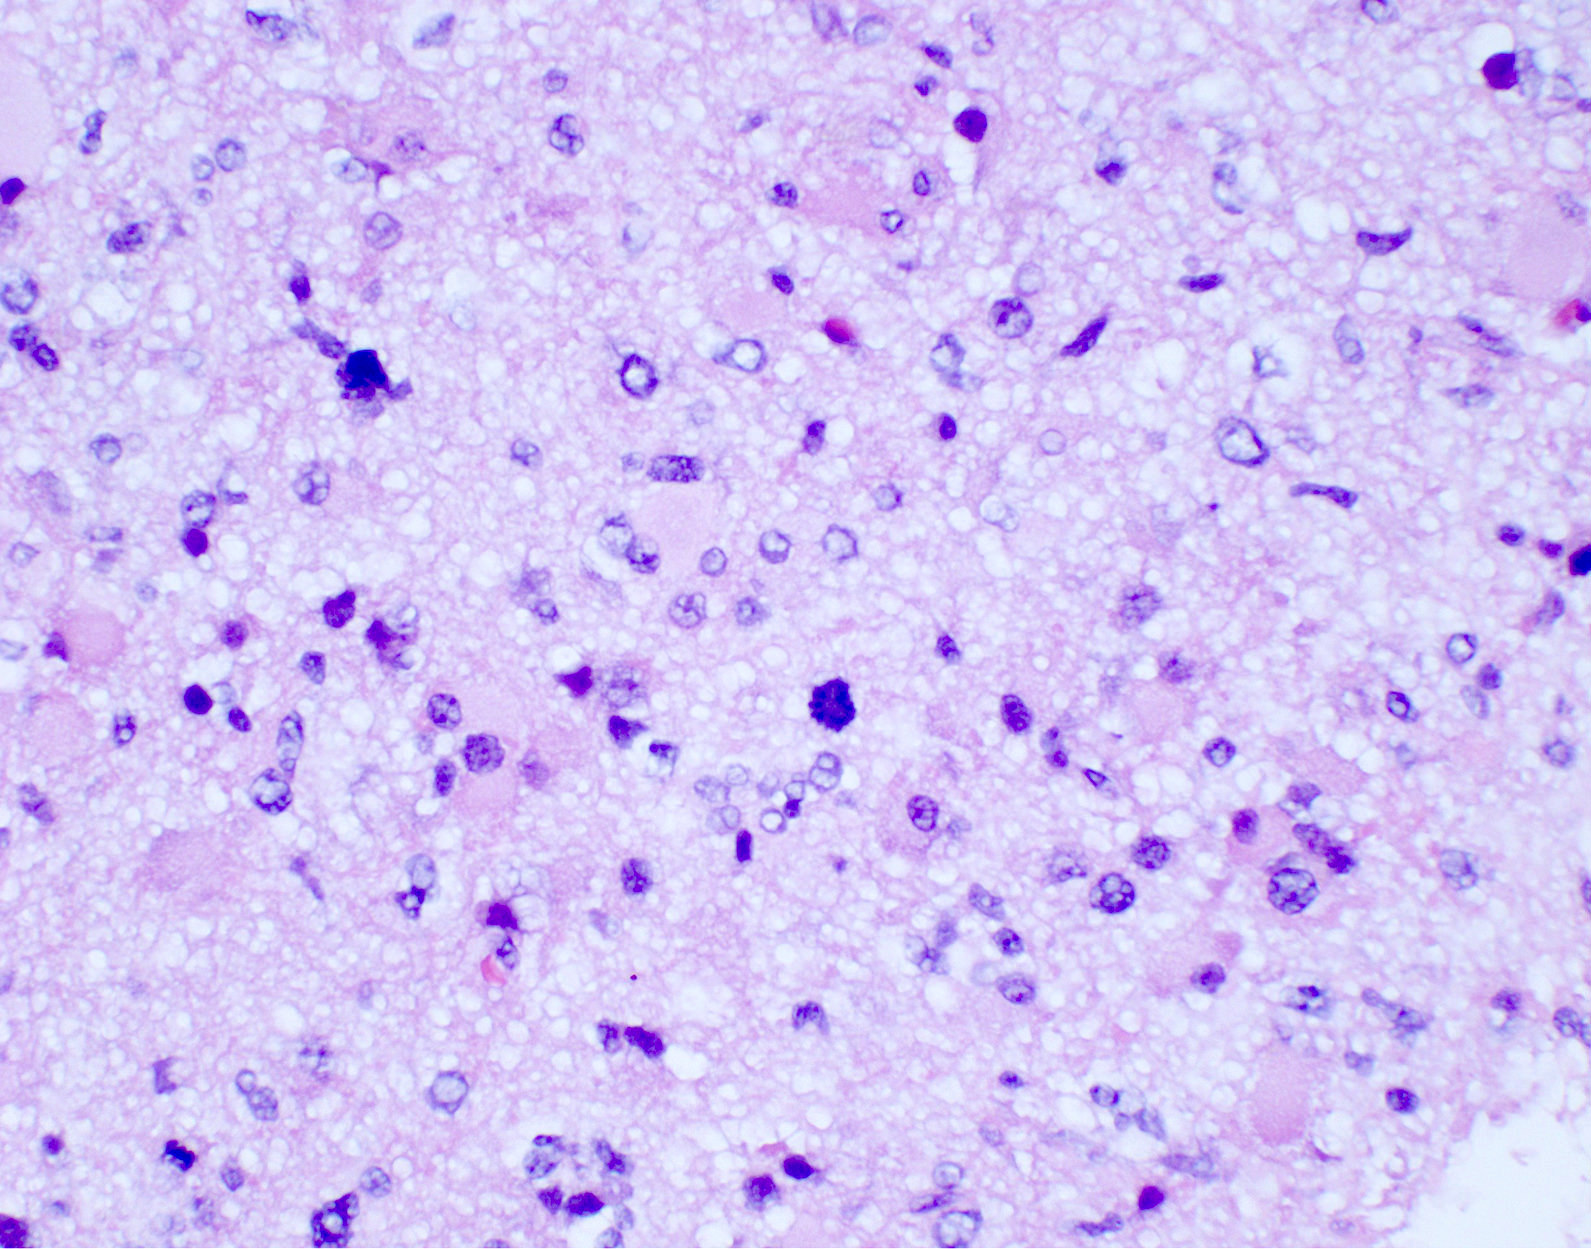

Microscopic (histologic) description

- Diffusely infiltrating tumor cells with oval to elongated astrocytic nuclei and varying appearance of tumor cytoplasm and fibrillar glial processes (Acta Neuropathol 2015;129:789)

- At the periphery, tumor cells may infiltrate in a diffuse single cell pattern, often with entrapped neurons and axons

- Cellular morphology is variable, even within a single tumor

- Commonly there is a mix of cells with elongated nuclei and fine fibrillar processes, cells with eccentric nuclei and glassy eosinophilic cytoplasm (gemistocytes), larger pleomorphic cells and small cells with scant cytoplasm

- May show oligodendroglioma-like areas

- Myxoid background and microcyst formation may be present

- Variable mitotic activity, cellularity and nuclear atypia depending on CNS WHO grade

- In small biopsy specimens, the presence of 1 mitosis may be sufficient for a CNS WHO grade 3 diagnosis, while the presence of a few mitotic figures in a large resection would not be sufficient for grade 3 designation (Acta Neuropathol 2020;139:603)

- Presence of necrosis or microvascular proliferation would be consistent with a CNS WHO grade 4 designation

Microscopic (histologic) images

Contributed by Eman Abdelzaher, M.D., Ph.D., John DeWitt, M.D., Ph.D. and Meaghan Morris, M.D., Ph.D.